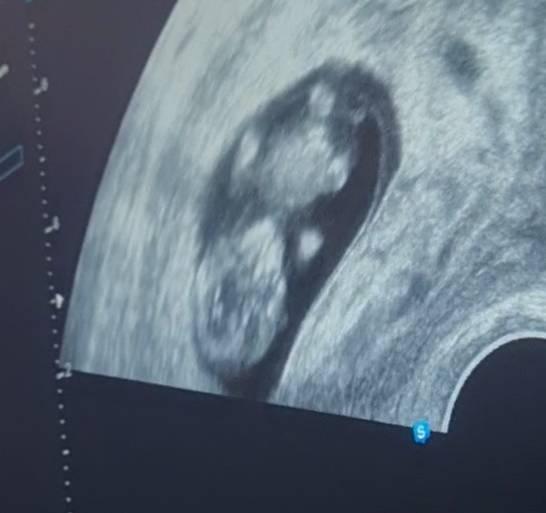

Heute hatte ich wieder einen tollen Ultraschall Termin und wollte einfach mal meine Freude mit euch teilen. Man liest ja doch oft negatives, was mich zum Teil auch verunsichert hat. Umso mehr hab ich mich über die strampelnde und zappelnde Bohne gefreut, über das Herzchen und über meine Frauenärztin, die mir immer ein gutes Gefühl gibt. Der einzige Wermutstropfen ist, dass mein Freund nicht live dabei sein darf. Dafür bekommt er ein Handyvideo, um wenigstens so dabei sein zu können. Wir freuen uns schon tierisch darauf, unsere Familien an Weihnachten mit dem Krümel zu überraschen

Bild zu Freude:) - Forum für Juli - Mamis